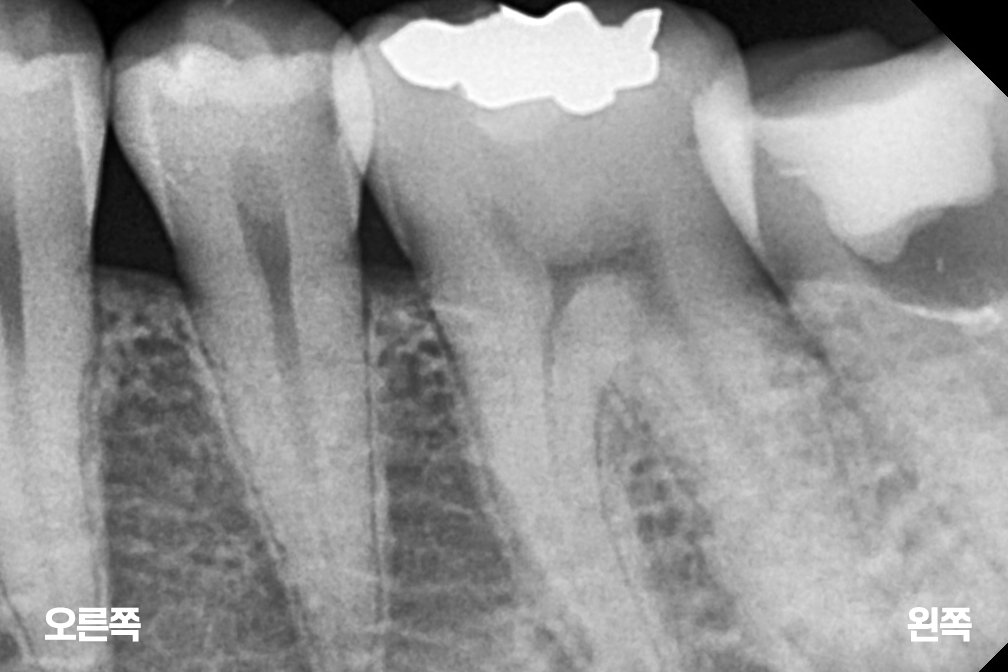

충치치료 왼쪽 아래 작은어금니(소구치) 충치치료

인레이

Before 2025년 6월 14일

After 2025년 7월 15일